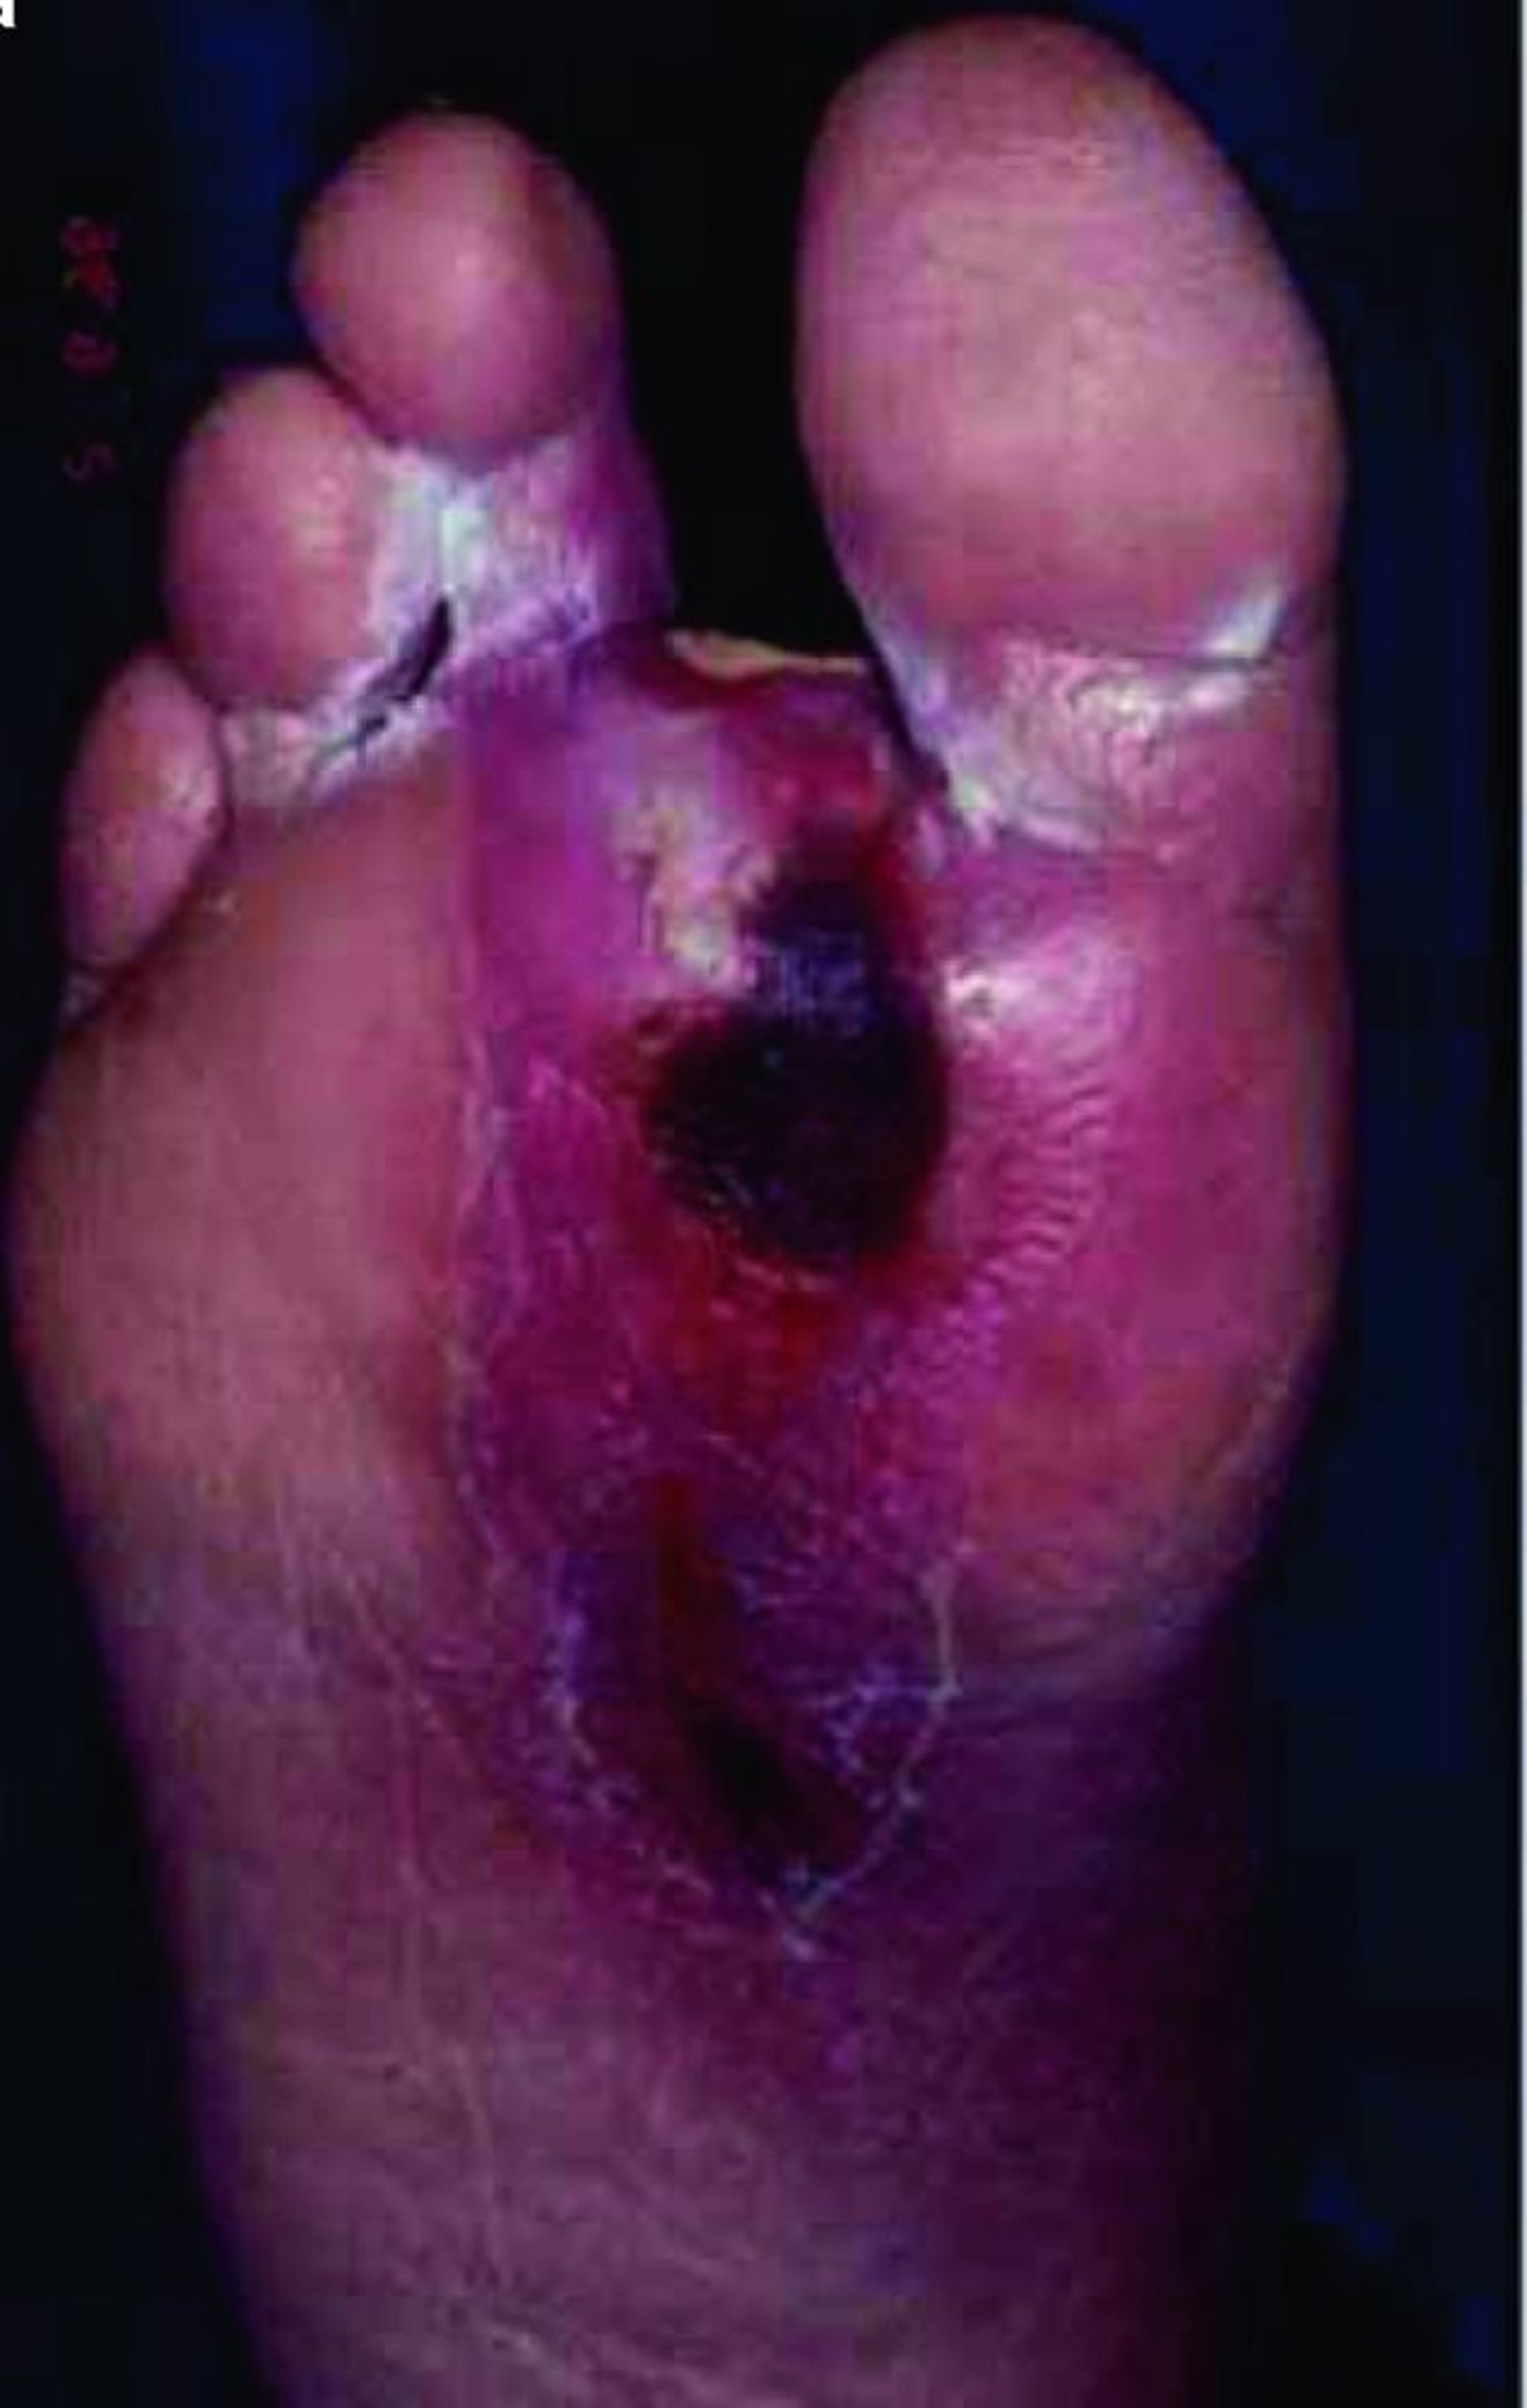

Fußulkus

Ein Patient mit Diabetes entwickelt häufig die mikrovaskuläre Störung, die Wundheilung schwer beeinträchtigen kann, sodass sich bereits kleine Verletzungen zu tiefen Ulzerationen mit einem erhöhten Infektionsrisiko entwickeln können, besonders in den unteren Extremitäten.